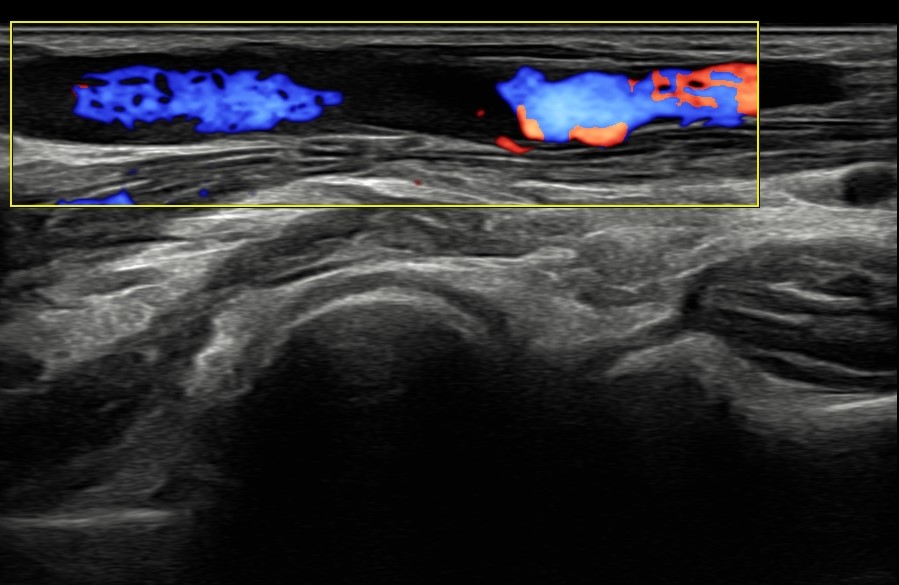

La venopunción ecoguiada se muestra como una técnica segura que ayuda a fomentar medidas de prevención cuaternaria y mejora el control emocional de los pacientes. Actualmente esta técnica se encuentra casi exclusivamente ligada a servicios como urgencias hospitalarias o UCI. Su implementación dentro de la Atención Primaria supone un proceso novedoso y destacable. Hoy en día, las enfermeras especialistas en Familiar y Comunitaria no cuentan en su periodo de residencia con una formación adecuada en esta técnica, por lo que el modelo de formación de formadores y su posterior integración en el EAP se plantea como un proceso innovador y pionero en Atención Primaria del Servicio de Salud del Principado de Asturias. Para iniciar la implementación de esta técnica, se ha realizado formación teórica y práctica conjunta entre residentes de medicina y enfermería.

La venopunción ecoguiada se muestra como una técnica asequible y útil en Atención Primaria, especialmente en casos de venopunción dificultosa.

Mejoría en flebotomías y canalizaciones venosas gracias a la correcta formación del EAP en técnica de venopunción ecoguiada.